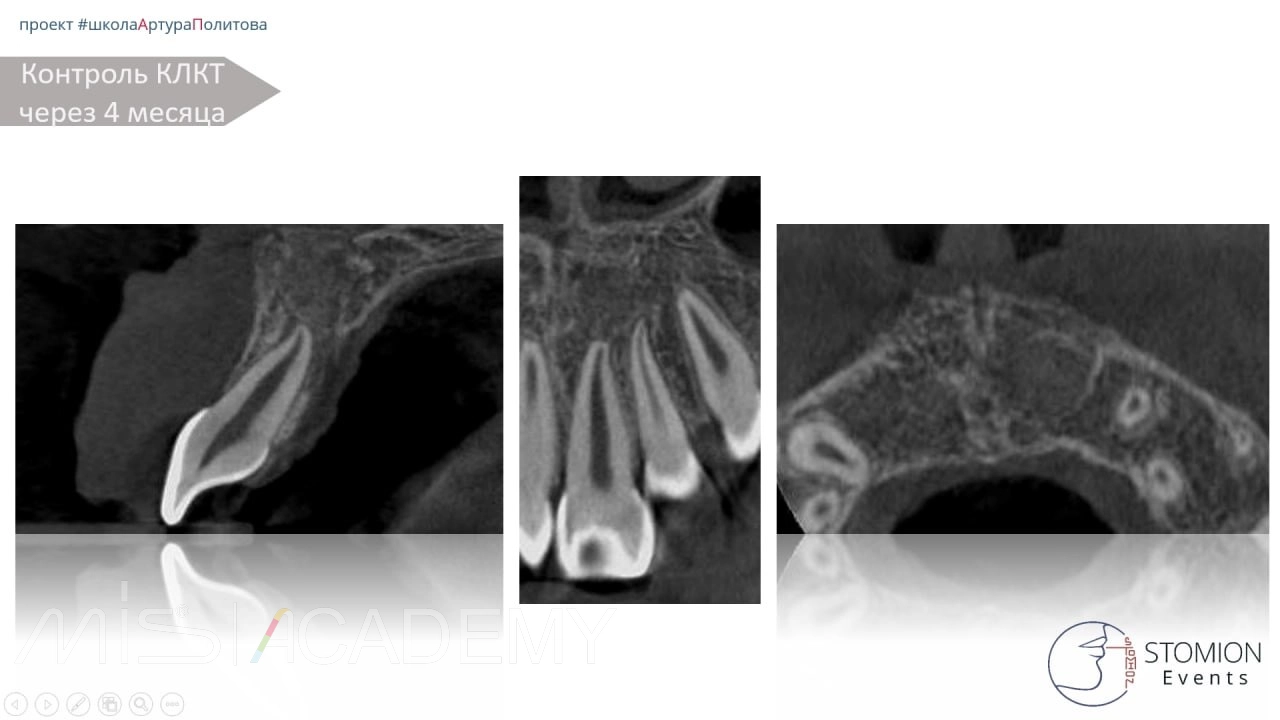

— Контрольное КЛКТ через 4 месяца.